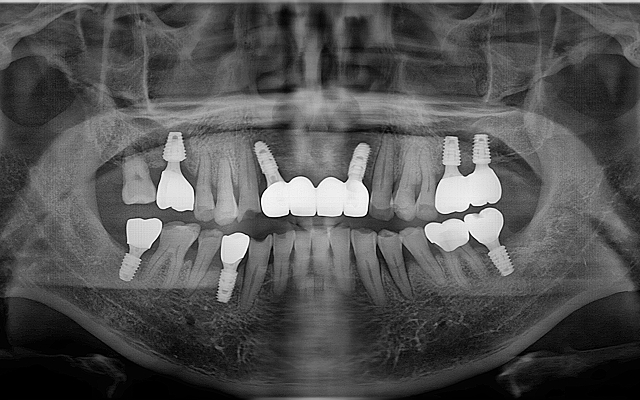

전악 케이스

- 상·하악 전체 보철 설계를 통해 정확한 교합(물림) 회복

- 심미·발음·저작 기능을 종합 고려한 자연스러운 전악 임플란트

고난도 뼈이식 케이스

- 정밀 영상 진단으로 결손 부위를 파악하여 안전하게 골이식

- 미세 수술 장비를 활용해 식립 안정성 및 성공률 향상

상악동 거상술 케이스

- 얇은 위턱 어금니 부위에 상악동을 거상하여 골량 보강

- 임상 경험을 바탕으로 합병증을 낮추고 예측 가능한 결과 도출